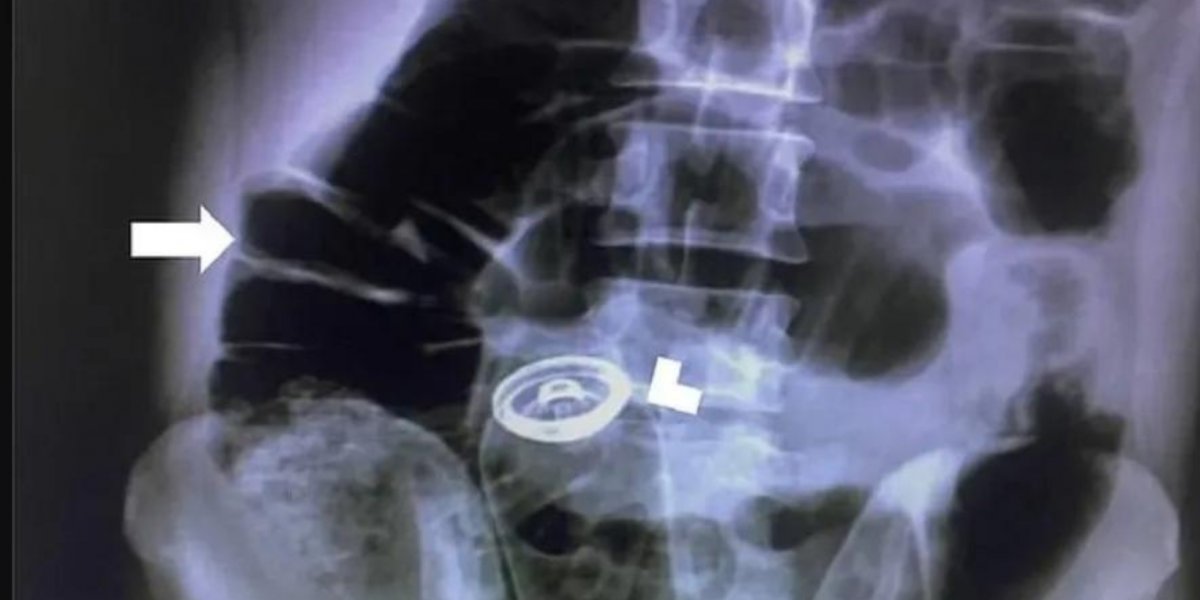

Foto: Reprodução/ Redes Sociais

O iraniano chegou ao hospital com dores estomacais “agonizantes” e confessou que havia inserido o objeto no ânus. Foi feito um raio x para encontrar o tubo, que foi removido cirurgicamente do estômago. Ele ficou um dia em observação no hospital e teve que passar por uma consulta com um psiquiatra antes de ter alta.